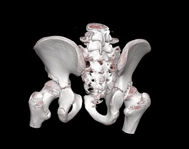

Figure 3 3D reconstruction Computed Axial Tomography of the right hip.

Preoperative planning is carried out through imaging studies, digital segmentation and 3D printing of the right hip (Figure 4), where the CAM-type morphology lesion can be evidenced. In the programmed operative room, under general anesthesia, in left lateral decubitus, an anterior approach to the hip is performed and dissection by planes up to the fascia, which is excised. Subsequently, an osteotomy of the greater trochanter is performed, release of the gluteus medius, the joint capsule is released, observing the femoral head with healthy articular cartilage; capsulotomy is performed and the Impingement test is performed under direct vision. Then, controlled hip dislocation is performed using a flexion and adduction maneuver, and resection of the anterolateral portion of the coxa magna is performed with an osteotome and shaver (DePuy-Synthes). Finally, hip reduction is performed and compliance is visualized under fluoroscopic vision in two planes, the greater trochanter is transposed and fixed with 2 6.5 mm cannulated screws (DePuy-Synthes), reduction compliance is visualized with fluoroscopic vision, and it is verified with direct visualization with a 3D model, suture is performed and the post-surgical cleaning with sterile dressings and gauze is performed, ending the procedure without complications. Radiological control is performed (Figure 5) and due to satisfactory postoperative evolution, medical discharge is decided after 24 hours. Radiographic control is performed at 6 months, where appropriate bone healing is evidenced (Figure 6).

Figure 4 3D printing of the right hip.